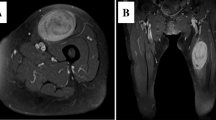

The patient-derived cancer models were generated from a 43-yr-old female patient with CCS in the National Cancer Center Hospital. The tumor was multinodular and located in the left thigh with invasion into the femur (Fig. 1 a). Multiple lymph node metastases were found by computed tomography (Fig. 1 b). RT-PCR suggested the fusion of EWSR1 with ATF1 in the tumor cells from the biopsy sample and surgically resected specimen (Supplementary Fig. 1). Tumor histology is shown in Fig. 1 c. Sanger sequencing confirmed the presence of this fusion in the biopsy sample (Fig. 1 d) and surgically resected specimen (Fig. 1 e). The patient was treated with left hip disarticulation and postoperative radiotherapy targeting lymph node metastases inside the pelvis. The patient died from the disease two mo after surgery. This study was approved by the ethics committee of the National Cancer Center, and written informed consent was obtained from the patient.

Characteristics of original clear cell sarcoma tumor tissue in this study. (a) T2-weighted magnetic resonance image showing a multinodular soft tissue mass in the left thigh (arrow). (b) Commuted tomography showed an enlarged external iliac lymph node (arrow). H&E staining of the surgically resected sample (c). Original magnification is 400×. Sanger sequencing of the gene fusion in surgically resected tumor (d) and biopsied (e) tissues.